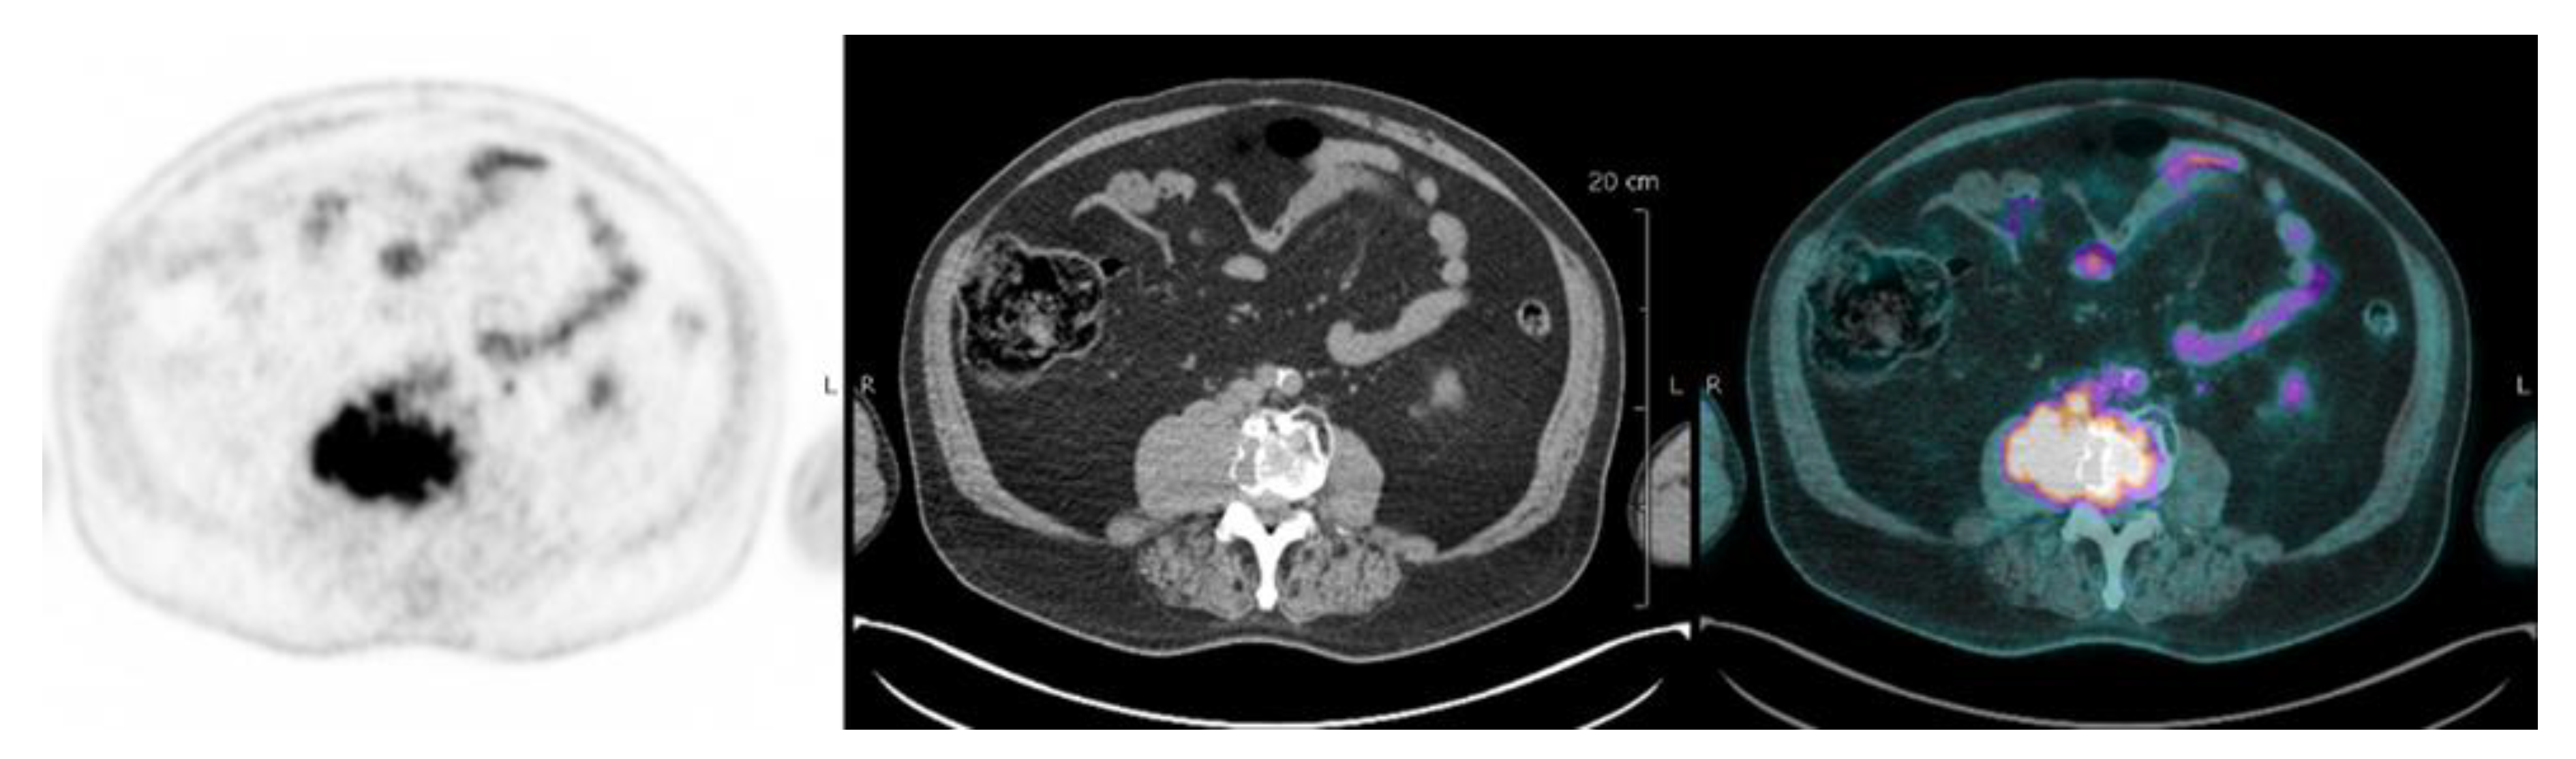

| Interpretation of PET Based on Prognostic Biomarkers | |||

|---|---|---|---|

| Lesions | Definition | Prognostic Biomarker | Reference |

| Focal lesion | Foci of uptake above the surrounding background noise on two successive sections with or without osteolysis on the CT image | Suggested as pejorative prognostic biomarker using cut off 3. | Bartel et al., 2009 [8] |

| Zamagni et al., 2011 [9] | |||

| Abe et al., 2019 [21] | |||

| EMD | Tissue invasion without contiguous bone involvement. | Presence of EMD suggested as pejorative prognostic biomarker | Zamagni et al., 2011 [9] |

| Moreau et al., 2017 [2] | |||

| Moreau et al., 2019 [19] | |||

| PMD | Soft tissue invasion with contiguous bone involvement. | Presence of PMD suggested as pejorative prognostic biomarker | Moreau et al., 2019 [19] |

| Diffuse medullary involvement | Homogenous diffuse uptake of the pelvic-spinal-peripheral skeleton higher than the liver background. | Prognostic value currently not demonstrated | |

| FL SUVmax | Maximal SUVmax of bone focal lesions | Suggested as pejorative prognostic biomarker using cut off of 4.2 | Zamagni et al., 2011 [9] |

| FDG-PET/CT abnormality | Presence of Focal lesion(s) and/or EMD lesion(s) and/or PMD lesion(s) and/or diffuse medullary involvement. | Absence of FDG-PET/CT abnormality considered as a favourable prognostic | Rasche et al., 2017 [16] |

| Abe et al., 2019 [17] | |||